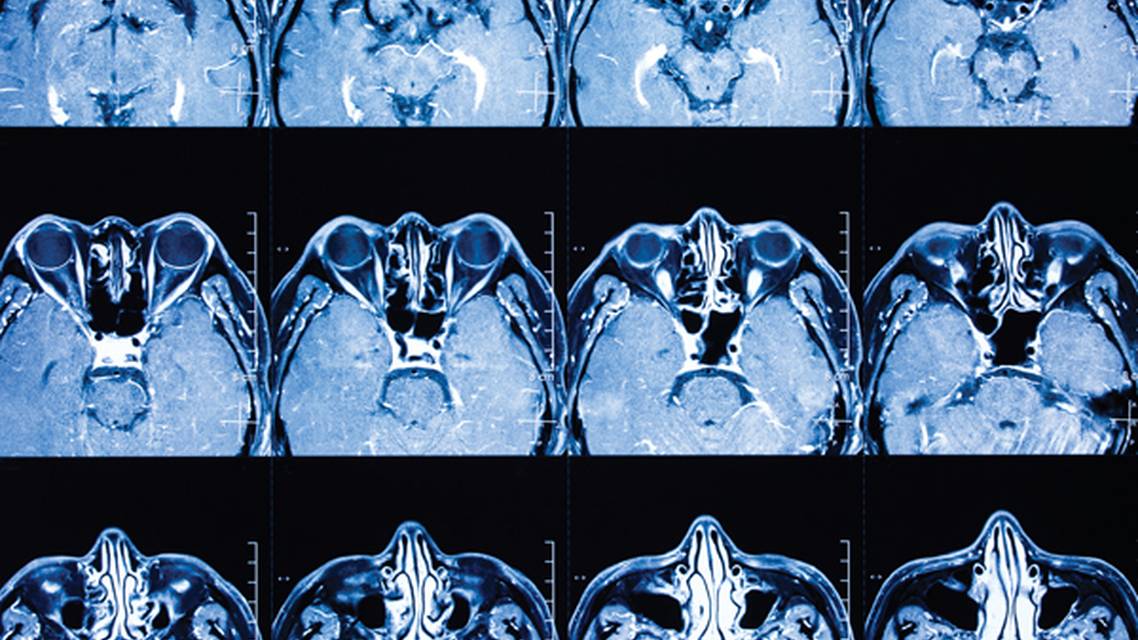

OCT revealed an average retinal nerve fiber layer of 110 µm OD and 106 µm OS, with a clean 30-2 visual field extending a full 360°. MRI displayed a subcentimeter complex pineal cyst with thin mural enhancement, along with a 7 mm x 9 mm enhancing nodule located posteriorly (Figure). Postcontrast imaging revealed no abnormal enhancement in the parenchymal, leptomeningeal meningeal, or pachymeningeal areas. The patient’s brain was morphologically normal. There was no empty sella morphology. The pituitary gland was normal in size for the patient’s age/demographic. There was no regional mass effect, midline shift, or hydrocephalus. ICP was measured at 19 mm Hg with the patient in a supine position. Normal ICP is typically between 7 mm Hg and 15 mm Hg. Upon confirmation of papilledema via fundoscopic examination, order a brain MRI to rule out a space-occupying lesion as the underlying etiology. Idiopathic intracranial hypertension is another potential cause of optic nerve edema and should be evaluated with a lumbar puncture.